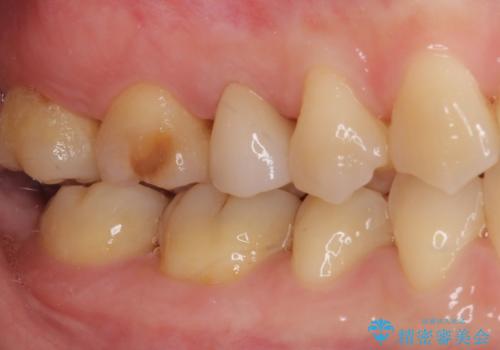

- 近医にて右上奥歯に大きなむし歯があると指摘されたとのことで来院された患者様です。

診査の結果、既に歯の神経は失活して変色しておりましたが、特に痛みは認めませんでした。

根管治療を行った後にオールセラミッククラウンにて補綴することとしました。